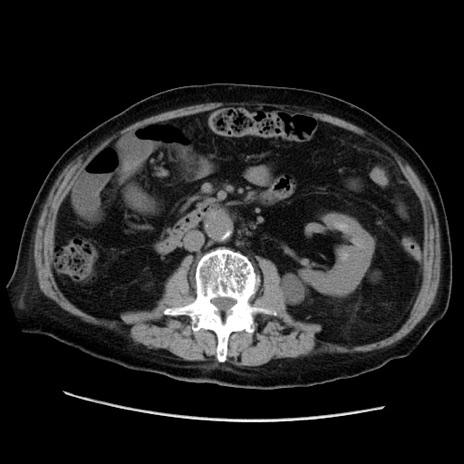

冠状断像

【症例】70歳代男性

【主訴】腹痛

【現病歴】肝硬変・肝細胞癌にてかかりつけの方。約9時間前に食後より腹痛出現。症状が徐々に増悪し、嘔吐出現したため来院。

【既往歴】肝硬変、肝細胞癌(RFA、TACE後)

【身体所見】意識清明、表情苦悶様、BT 36℃、BP 129/78mmHg、P 88bpm、SpO2 97%(RA)、右上腹部から心窩部にかけて圧痛あり、反跳痛なし、筋性防御あり。

【データ】WBC 5800、CRP 0.16